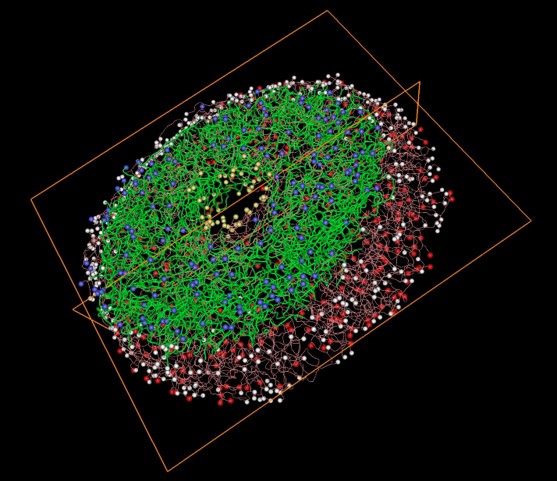

• A workflow for 3D reconstruction and quantification of the monkey optic nerve head vascular network

• PY Lee, Y Hua, BL Brazile, B Yang, L Wang, IA Sigal

• ASME Journal of Biomechanical Engineering,